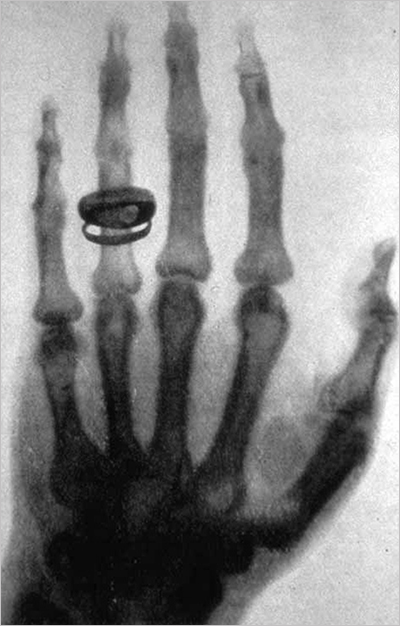

여기서 뢴트겐은 한 가지 아이디어를 떠올리게 되는데, 당시 사진건판이 발명되어 사진관에서 사진을 찍는 것이 유행이었습니다. 뢴트겐은 이 사진건판을 이용하여 새로운 빛을 활용해 감광 사진을 찍는 아이디어를 떠올렸습니다. 그 결과는 우리에게 너무나 잘 알려진 바로 그 사진에 담겨 있지요. 약혼녀의 손을 찍은 이 사진은 뢴트겐에게 새로운 빛이 존재한다는 명백한 증거가 되었고, 이 미지의 빛은 미지의 선이라는 의미로 X선(X-ray)이라고 부르게 되었습니다. 당시 뢴트겐의 X선 발견은 사회적으로 큰 충격이었는데, 사생활을 크게 침해할 수 있다는 걱정과 그에 관련한 광고까지 나왔을 만큼 사회문화적으로 불투명한 물질의 내부를 들여다볼 수 있다는 사실은 적잖은 충격이었습니다.